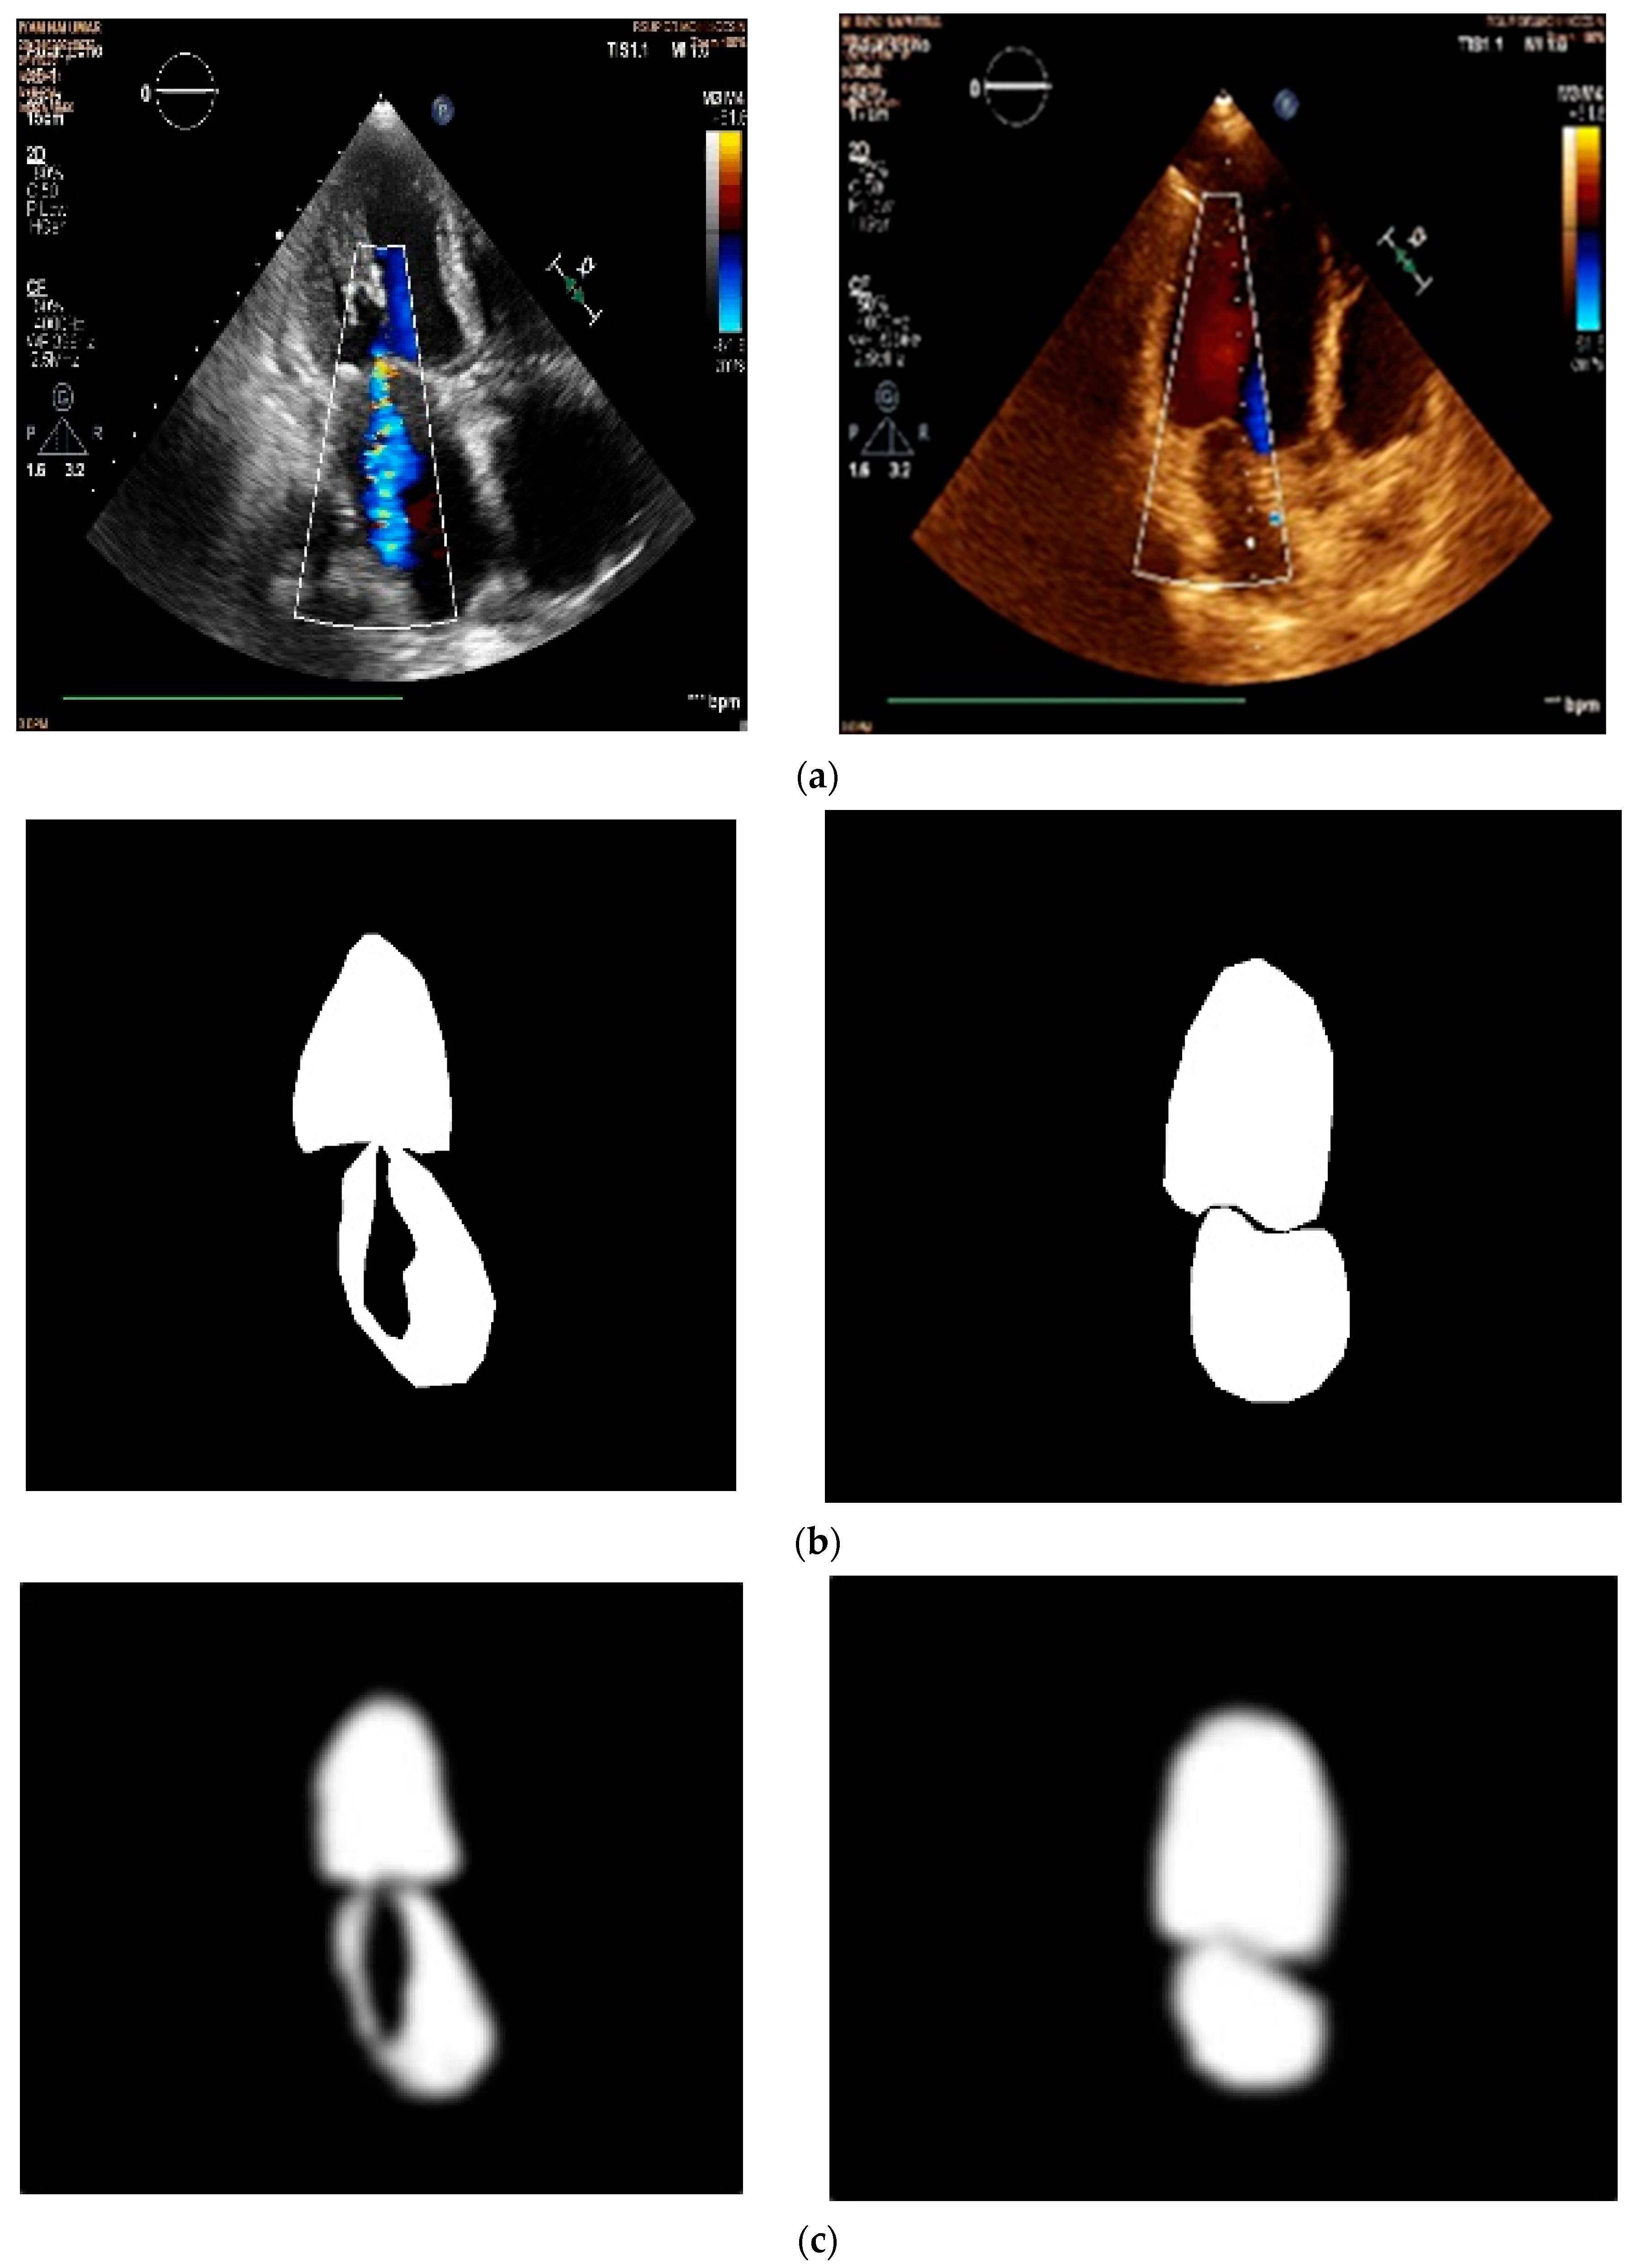

2.1. Data Acquisition

2.2. Data Pre-Processing

3.1. Results